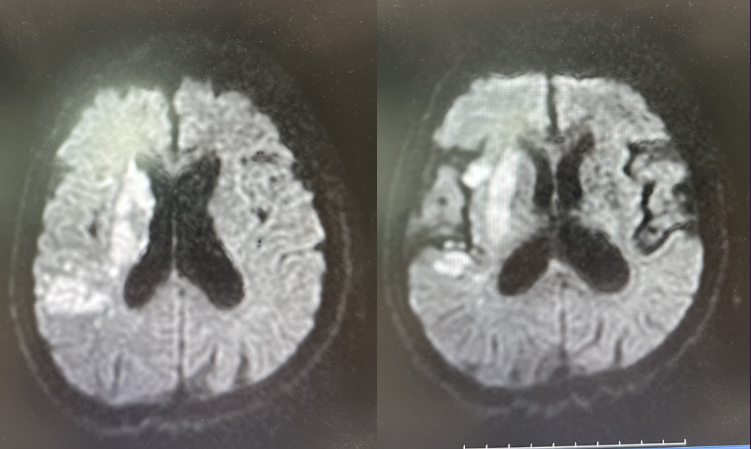

图四:48小时头颅核磁+血管

术后48小时查头颅核磁,提示右侧大脑半球大面积脑梗死,右侧大脑中动脉充盈良好。